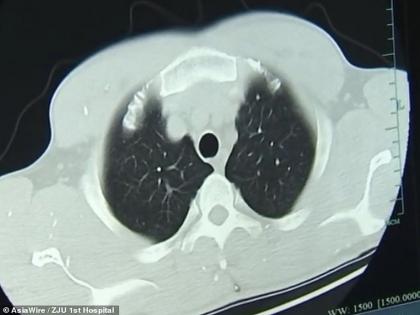

झू च्या शरीरात ७०० पेक्षा जास्त टेपवर्म आढळून आले. हे टेपवर्म त्याच्या मेंदू आणि लिव्हरपर्यंत पोहोचले होते. रिपोर्टनुसार, टेपवर्मची अंडी आधी पोटावर्यंत पोहोचली आणि त्यानंतर रक्ताच्या माध्यमातून संपूर्ण शरीरात पसरले. डॉक्टरांनी सांगितले की, हे टेपवर्म अर्धवट शिजलेल्या डुकराच्या मांसाच्या माध्यमातून झू च्या शरीरात शिरले होते आणि नंतर त्यांची संख्या सतत वाढत राहिली.

डॉक्टरांनुसार, झू टीनिएसिस नावाच्या आजाराने पीडित होतो. हा आजार टेपवर्म टीनिया सोलियमच्या संक्रमणामुळे होतो. झू ने सांगितले की, त्याने एक महिन्याआधी डुकराचं मांस खाल्लं होतं. मात्र, ते मांस पूर्णपणे शिजलेलं होतं की नाही हे त्याला माहीत नव्हतं. झू हा एक मजूर आहे.

झेझियांग युनिव्हर्सिटी स्कूल ऑप मेडिसिनमधील डॉक्टर हुआंग जियानरॉन्ग यांच्यानुसार, झू ला अॅंटी-पॅरासिटीक औषधे देऊन त्याच्या शरीरातून टेपवर्म नष्ट केले गेले. सध्या यांचा प्रभाव त्याच्या शरीरावरून कमी होण्यासाठी उपचार सुरू आहेत.